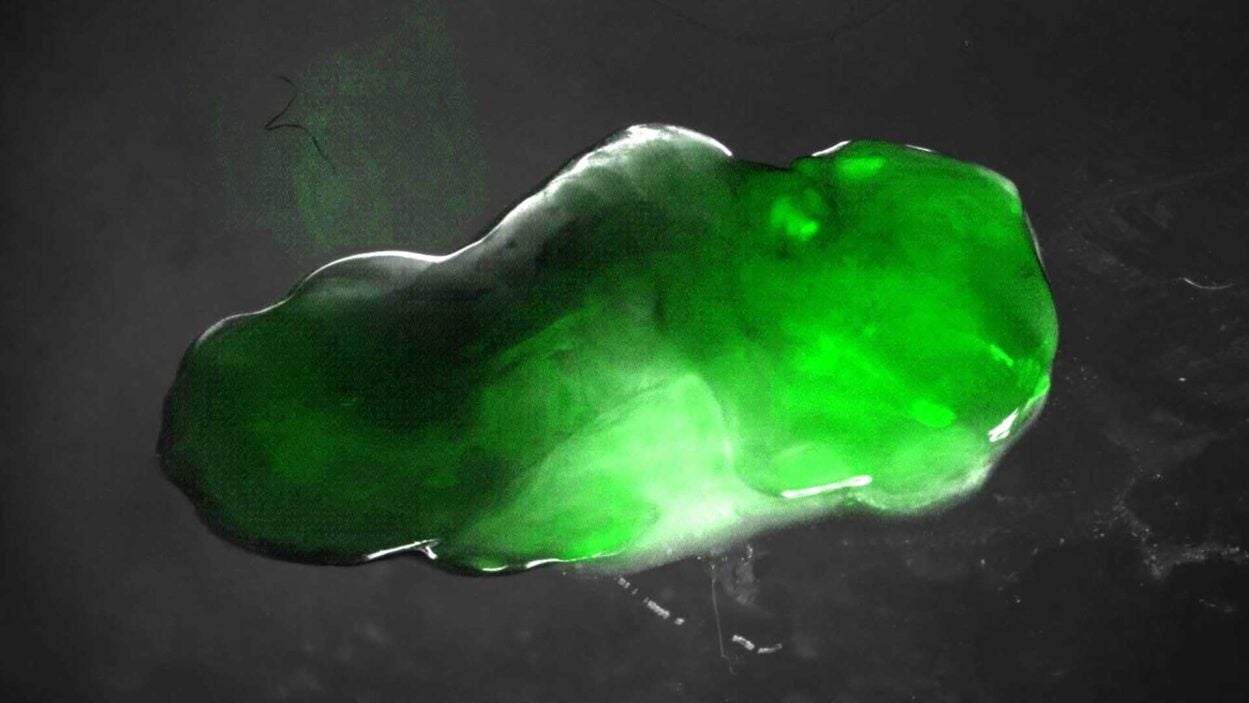

That’s no moon! So what is it really? Read on to find out. Read the story »

That’s not the Starship Enterprise burning up in space. It’s an up-close look at precancerous pancreatic lesions and the mucus they produce. Read the story »

Mucus is not just snot. CSHL scientists have discovered some pancreatic cancer cells depend on it. The finding may open a new therapeutic avenue. Read the story »